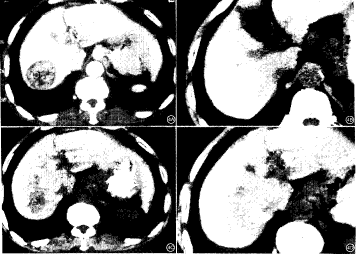

图3 患者 男,58岁。患乙型肝炎及肝硬化9年,经超声及活检证实为原发性肝癌。A.CT增强扫描见肝右叶不规则形态混合密度病变。B.应用超液化碘油和普通碘油以1∶1的比例混合后栓塞,即刻摄片见碘油大多数积聚于病灶内,但病灶周围也见很多碘油分布。C.栓塞后25天CT复查见病灶有缩小,病灶内外均见碘油沉积图4 患者 男,56岁。影像学及细胞学检查证实为肝右叶原发性肝癌。A.术前CT增强扫描见肝右叶不均匀强化病变。B.经用超液化碘油行TAE治疗后,21天复查,病灶内碘油积聚良好。C.45天时复查,病变有缩小,但病灶内大部分碘油已消失,仅原病灶边缘部仍有部分碘油沉积。D.第2次栓塞后碘油沉积于病灶内